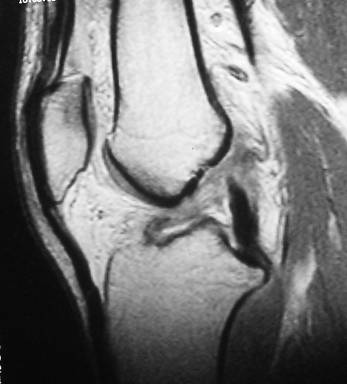

ACL tear